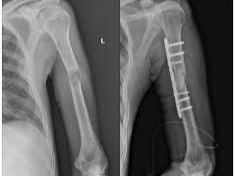

어깨에 골절이 발생하면 일상 전체가 마비되는 기분을 느끼는 것도 무리는 아닙니다. 특히 쇄골, 상완골 근위부, 견갑골 부위에 골절이 생기면 수술이 필요하며, 수술 이후의 재활과 물리치료는 단순히 통증을 없애는 것을 넘어, 관절 가동 범위의 회복과 장기적인 기능 정상화를 위한 핵심 단계입니다. 또한 어깨 골절 수술 이후 본격적으로 시작되는 재활 치료와 도수치료의 현실적인 문제는 ‘비용’과 ‘보험 적용 여부’입니다.

어깨를 조금씩 움직일 수 있는 단계로 넘어가며 본격적인 재활이 시작됩니다. 운동 범위를 서서히 넓혀야 하며, 이 과정에서 **수동적 운동(passive exercise)**과 **능동보조 운동(assisted active movement)**이 이루어집니다. 이때부터는 물리치료와 도수치료의 필요성이 점점 커집니다.